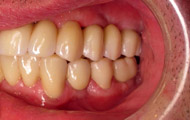

Exemple d’une réhabilitation complète implantaire

Situation clinique terminée